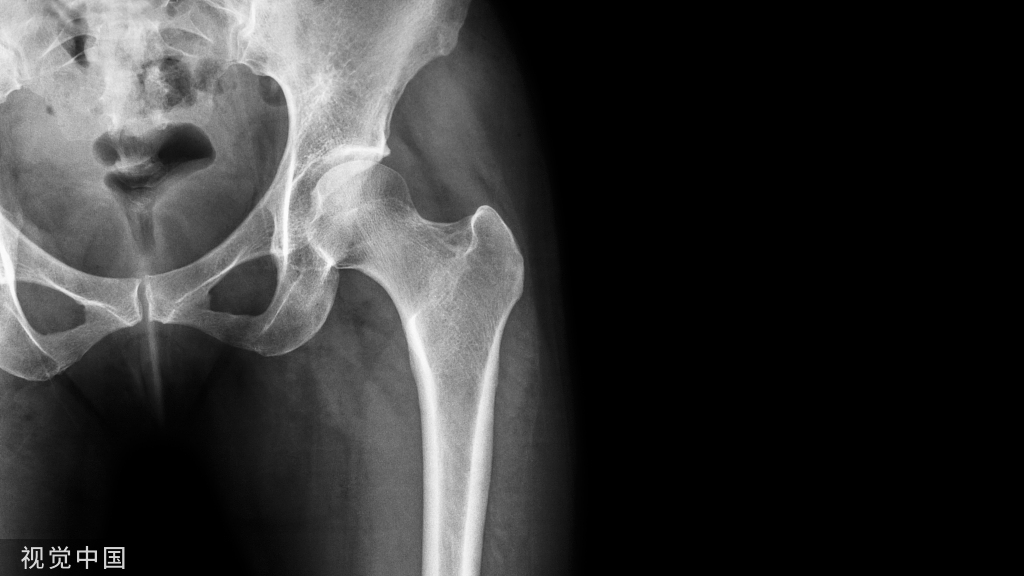

53y  M  车祸损伤左侧胫腓骨远端开放性粉碎性骨折Gustilo IIIB;AO 43-C3

Stage I清创、外支架固定

• 骨缺损6cm

• 软组织缺损

• 距骨关节面外露

带抗生素骨水泥旷置游离股薄肌瓣覆盖

术后复查外支架维持稳定Spacer位置理想力线良好